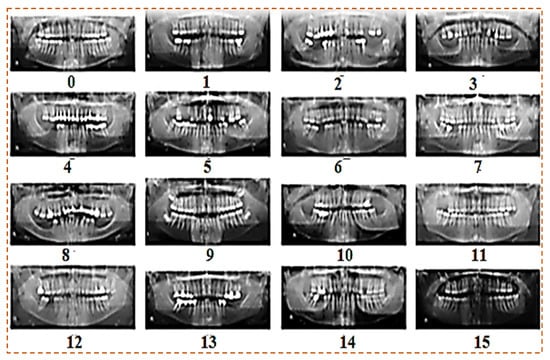

The dataset contains OPG dental panoramic X-rays collected from clinics. Some OPGs were taken with a DSLR camera, whereas others were obtained from clinics in soft form. All the images are high resolution. The custom dataset contains 1200 images of patients ranging in age and teeth problems. The Figure 2 show our custom dataset:

4.2. Image Augmentation

Augmentation is the process of increasing the size of a dataset to meet our needs. We collected approximately 800 images from various clinics. Following that, we used some augmentation functions to increase the number of images. We ended up with 1200 images in total. Custom dataset after augmentation are shown in Figure 3. We used the image data generator function for augmentation with the following parameters:

Figure 3. Custom dataset after augmentation.